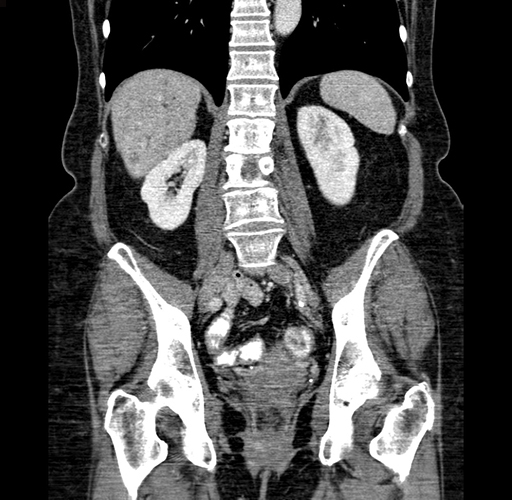

Pre-Chemo: Axial Venous

Pre-Chemo: Coronal Venous